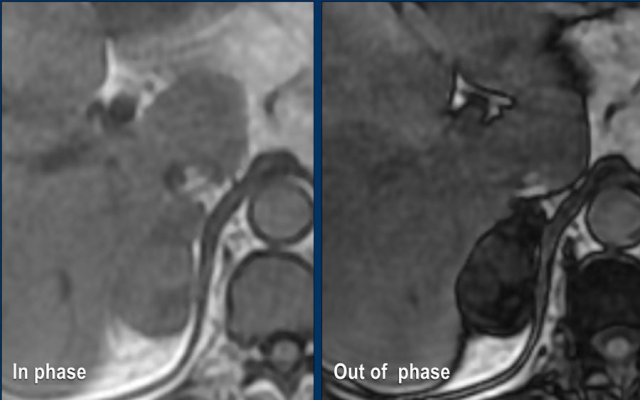

MRI Out-of-phase imaging

Lipid-poor adenomas can also be diagnosed with out-of-phase imaging.

They contain enough microscopic fat to cause a signal drop on out-of-phase imaging compared to in-phase imaging due to the chemical shift artefact.

These images are of a 65- year-old female patient with an incidental discovery of a right adrenal mass on an abdominal ultrasound performed for renal stones.

The presence of microscopic fat is demonstrated by the signal drop on the opposed-phase image.

The patient was followed for 2 years, because the lesion is slightly inhomogeneous and measures 5.2 cm.

The lesion did not change in size and was not hormonally active.

It was diagnosed as a lipid-poor adenoma.

MRI performed for a left adrenal incidentaloma discovered on a non-contrast and arterial phase CT scan in a 61-year old male patient with an abdominal aneurysm.

On the non-contrast CT density was 18 HU.

T1 out-of phase image shows subtle inhomogeneous signal drop compared to in-phase.